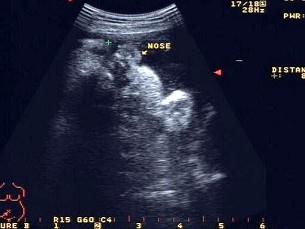

问题 图为胎儿鼻唇区显像,“+”处标出的为?(?)

选项 A.鼻唇沟 B.伪像 C.右侧鼻孔 D.唇裂 E.以上都不是

答案 D